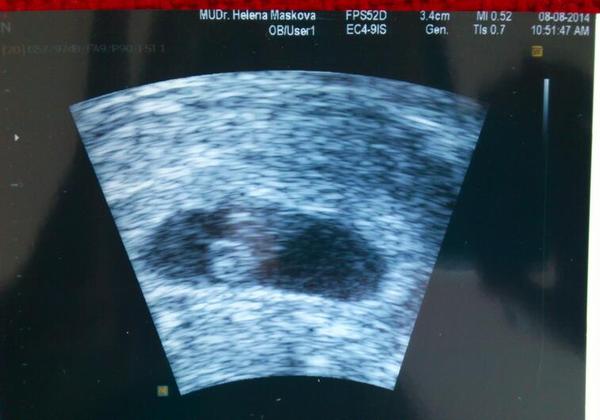

Ahoj holky moje, tak jsme doma,, juchů buší nám jako o život, podle UTZ jsme 7+3, podle počítání dle OPU 7+0, 29.8. už budu mít 1.poradnu u své doktorky, máme se rozhodnout ohledně těch testů na vývojové vady, v brně to dělají vše v 1 den výsledky jsou večer,nebo u své doktorky v 10.tt krev a ve 12.tt UTZ a pak se to vyhodnotí rozdíl cenový 1500,-/1000,- akorát mám zvětšený levý vaječník má asi 8 cm, to je prý to homonál.stimulací,mělo by se to postupně stahovat a zmenšovat, ale kdyby byl problém - bodavá bolest, něco jako kolika okamžitě na pohotovost.

@bubulina1983 No paráda, moc gratuluju, krásná fotečka 🙂

@bubulina1983 ahoj, no páni, to je úžasná fotka 🙂 moc gratuluji 🙂 je dobře, že sis došla ke své doktorce. Alespoň víš, co a jak a nemusíš se strachovat. Taky bych se přikláněla k testům v Brně. Takový rozdíl co se týká financí to opravdu není a alespoň budeš mít výsledky hned a nebudeš muset zase na něco čekat. A to přeci víš, jak se to čekání vleče 😀

@elisc + @luca16 + @andreee86 + @debee - holky díky moc za podporu, včera mi spadl balvan ze srdce, srdíčko ťukalo a doktorka se mě ptá vidíte to tady, ještě se ověřovala jestli to taky vidím, byla strašně hodná, vzala mi stěry a za 3 týdny už mám 1.poradnu 😀 no s těma testama uvidíme, něco si o tom přečtu a apk se rozhodneme..

@bubulina1983 Krásná fotečka!!! Gratuluji mamino!!!